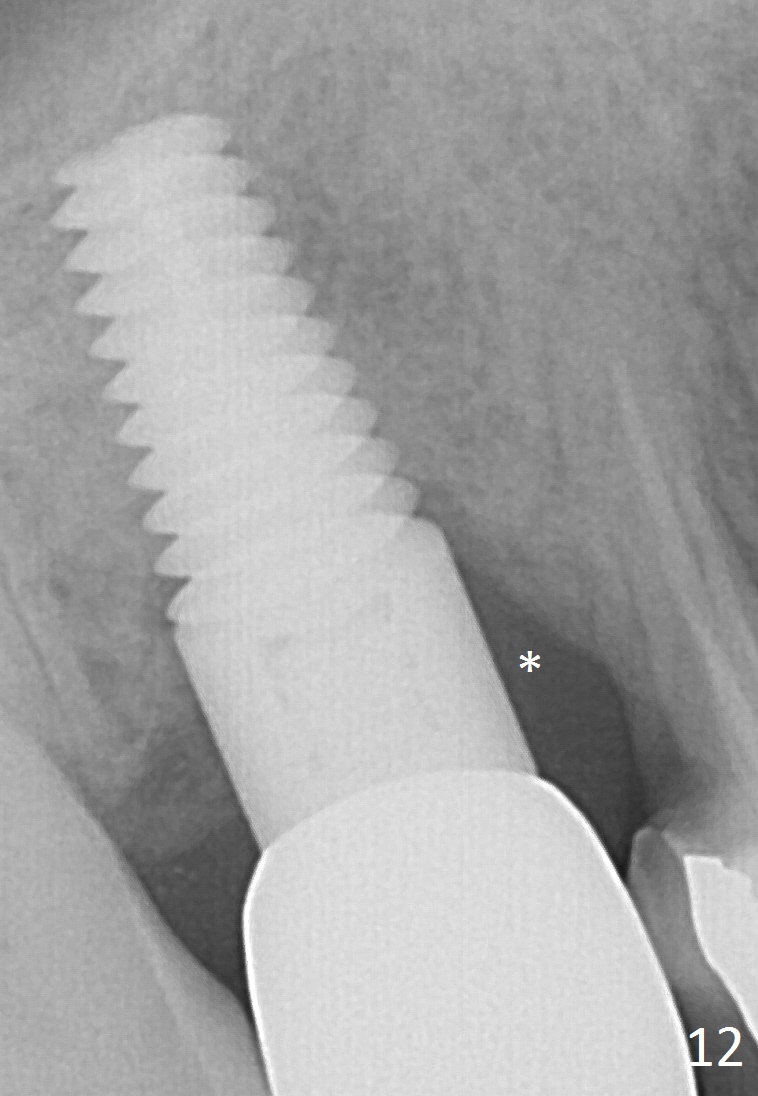

Four months after implant removal, the bony defect appears to increase (Fig.5). Reamers (Fig.6 R)and osteotome (Fig.7 O) are short of the sinus floor (arrowheads). A 5x14 mm tapered implant is placed with primary stability (Fig.8 I). The implant is placed ~ 2 mm deeper (Fig.9). No bone graft is used for sinus lift. There is no complication. The sinus floor appears to be repaired 4.5 months postop (Fig.10). Fig.11 (trimmed from panoramic X-ray) is taken 1 year 7 months post cementation. The bone remains stable 4 years 2 months post cementation (Fig.12); the mesial defect is most likely related to extraction trauma (*).